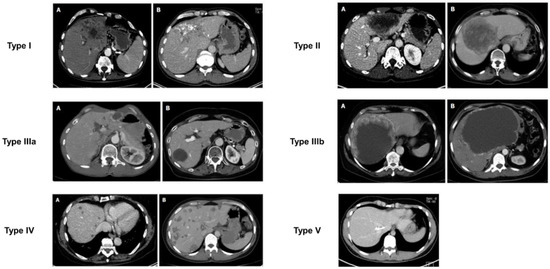

Besides the US, computed tomography (CT) is presently the preferred diagnostic imaging among the available methods, as it is capable of detecting the highest number of lesions and clearly distinguishing characteristic calcifications [111,112]. Abdominal CT is more suitable for identifying calcifications and preoperative assessment. CT scan primarily relies on the determination of lesion size, rather than on the accurate assessment of AE proliferation and infiltration activity. In 2016, Graeter et al. [113] proposed five classifications for CT imaging of hepatic alveolar echinococcosis (Figure 5). Type I: diffuse infiltrating, Type II: primarily circumscribed tumor-like, Type III: primarily cystoid, Type IV: small-cystoid/metastatic, Type V: mainly calcified. After conducting a retrospective analysis of 228 patients with hepatic alveolar echinococcosis, they revealed that the most frequently encountered CT morphological pattern was the diffuse infiltration pattern (Type I), followed by the primarily circumscribed tumor-like appearances (Type II). The mainly calcified appearance (Type V) was observed less frequently. The E. multilocularis Ulm classification for computed tomography (EMUC-CT) offers the basis for the systematic description of the CT morphology of AE lesions of the liver [114]. A study has shown that there is a close correlation between the patterns of AE according to the EMUC-CT classification and the different histological patterns of AE infections [79]. The CT types mark consecutive stages of infection, which progress over time. The classification of calcifications in AE observed on CT is shown in Figure 6.